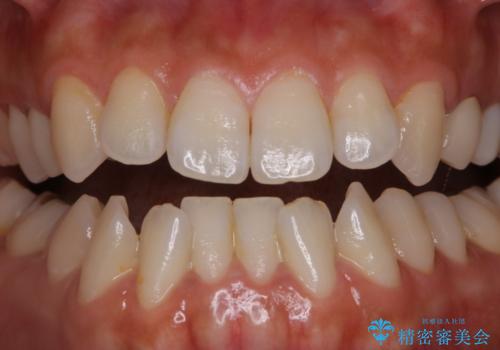

矯正治療が終わったタイミングでPMTC

担当医 歯科衛生士